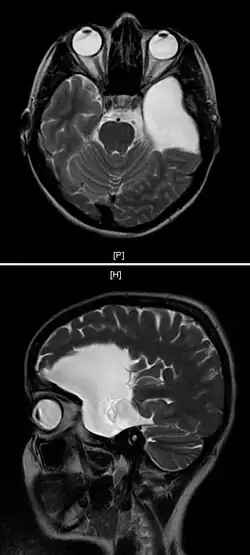

| An MRI of a 25-year-old woman with left frontotemporal arachnoid cyst. | |

Diagnosis is principally by MRI. Frequently, arachnoid cysts are incidental findings on MRI scans performed for other clinical reasons. In practice, diagnosis of symptomatic arachnoid cysts requires symptoms to be present, and many with the disorder never develop symptoms.